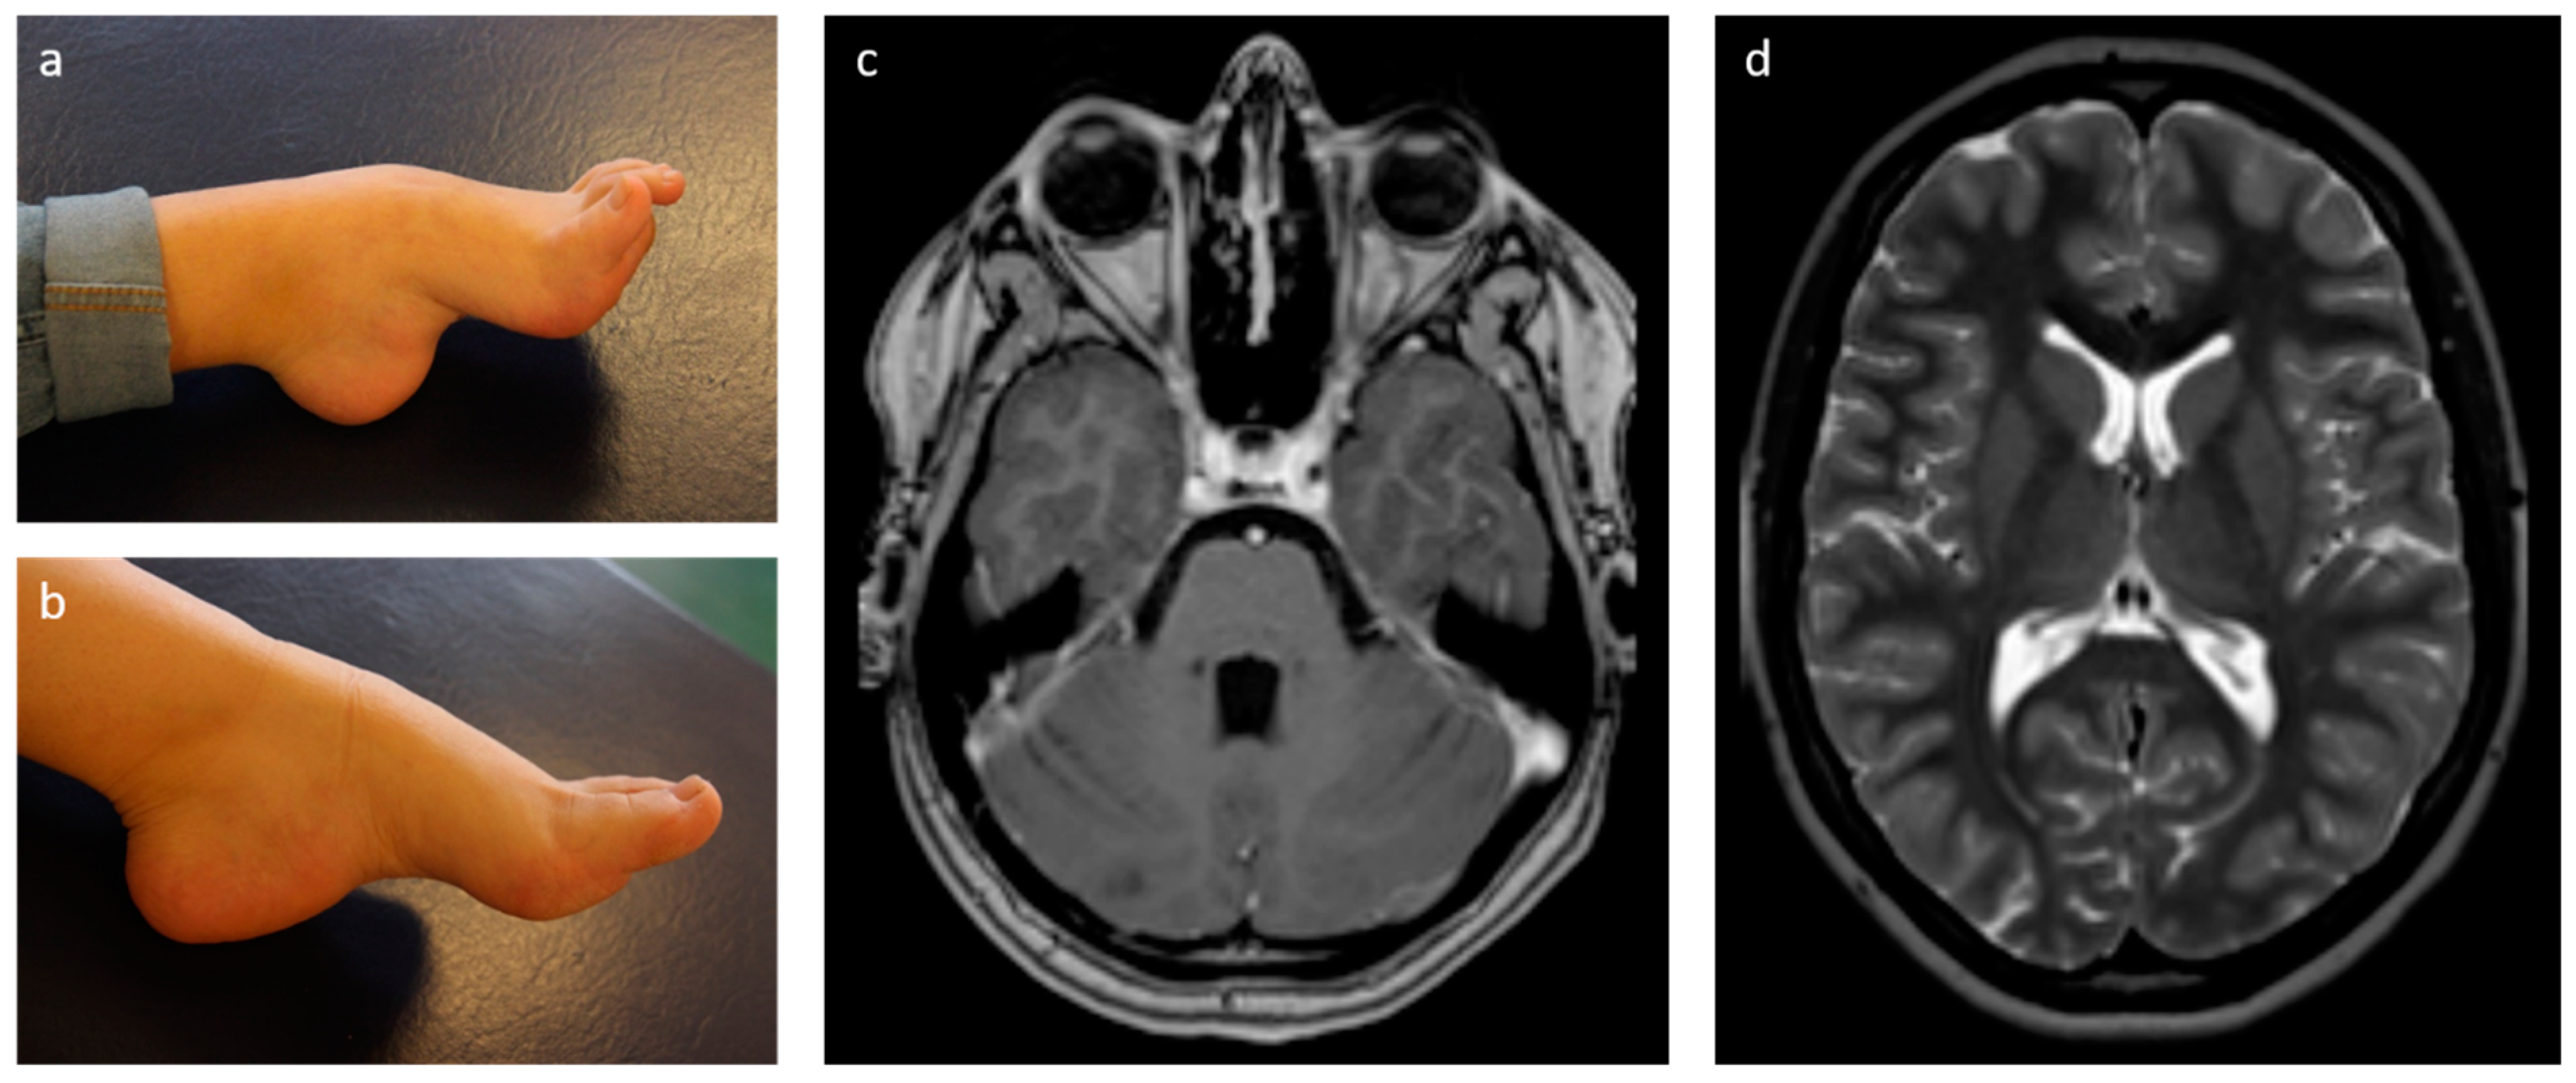

2.1. Case Presentation